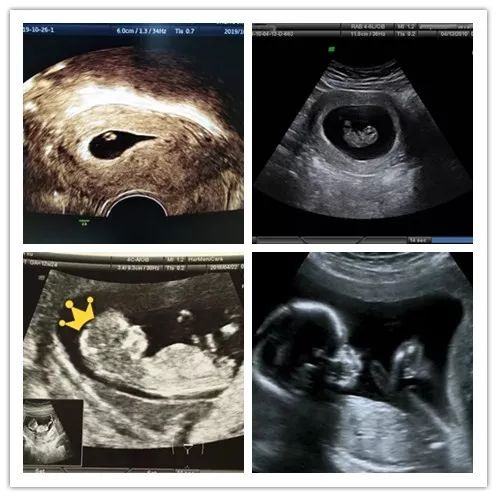

B超排除宫外孕

通过超声波检查,能看到胚囊在子宫内的位置,是否有卵黄囊,排除宫外孕。另外,还可以看到胚胎数目,以确定准妈妈是否孕育了双胞胎。

看胎心胎芽

通过超声波检查看胎芽,有无原始心管搏动。